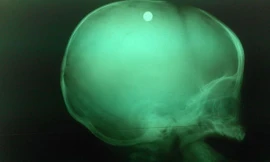

TP - Hôm 6/5, ê kíp bác sĩ Khoa Ngoại thần kinh, Bệnh viện Nhi đồng 2 TPHCM đã phẫu thuật khẩn cấp cứu sống bé trai 6 tháng tuổi ở Bình Phước bị bắn vào đầu.